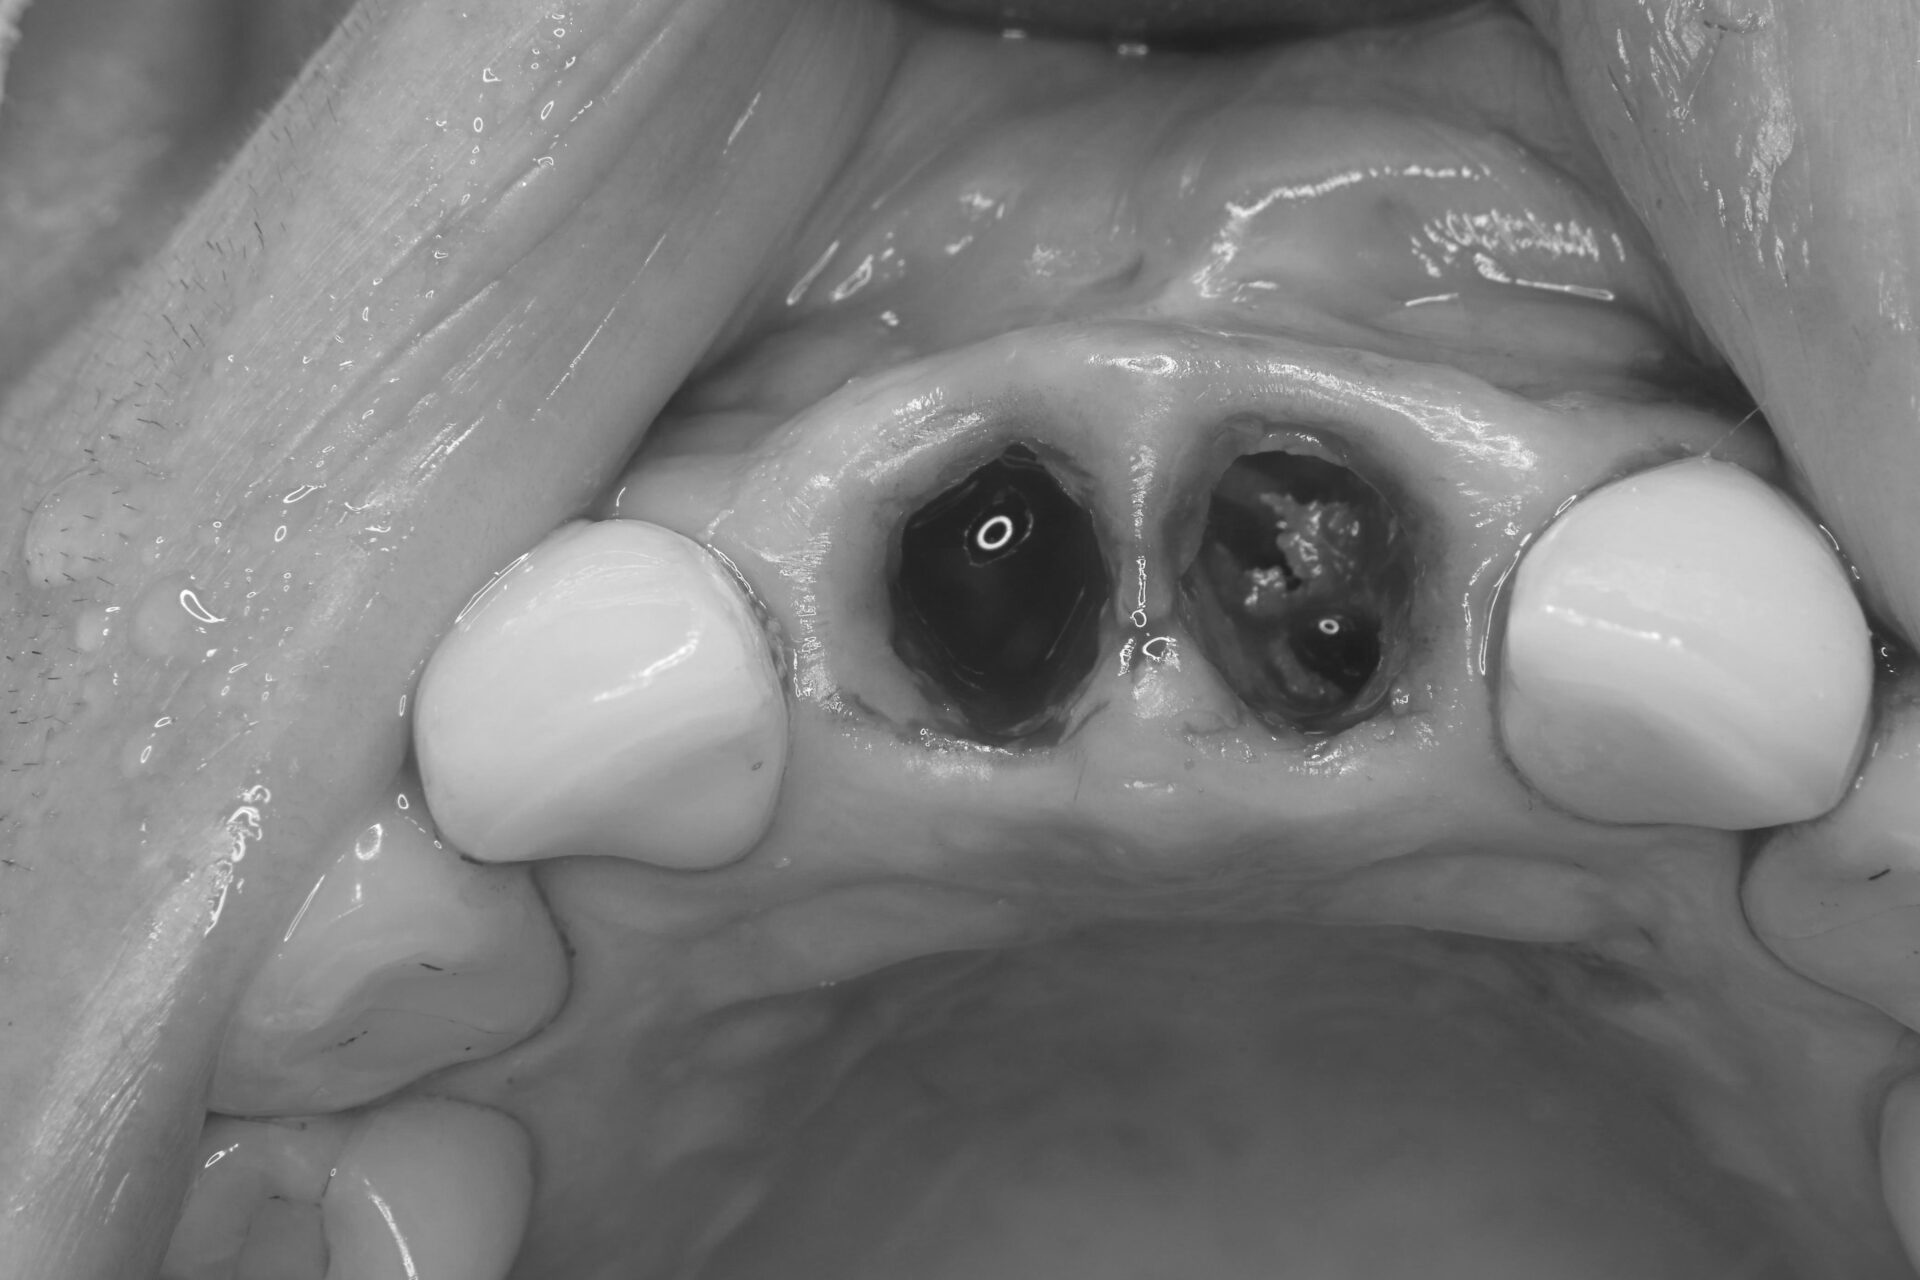

抜歯後の状態

保存不可能な歯を丁寧に抜歯し、周囲の骨や歯肉をできるだけ温存しました。抜歯窩の清掃を行い、インプラント埋入の準備を整えます。